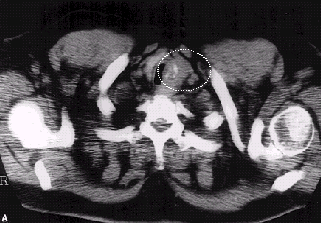

경부 전산화단층촬영(CT), 양전자방출단층촬영/전산화단층촬영복합영상(PET/CT)

전산화단층촬영(CT), 양전자방출단층촬영/전산화단층촬영복합영상(PET/CT) 등 영상검사를 하면 갑상선 결절에 대한 추가적 정보를 얻을 수 있고 암일 경우엔 림프절 전이 여부, 주변 조직 침범 여부, 다른 장기로의 전이 여부 등을 알 수 있으나, 일반적으로 결절의 감별 진단에는 이들 검사를 사용하지 않습니다. PET/CT란 양전자방출단층촬영(PET, positron emission tomography) 스캐너와 전산화단층촬영(CT, computed/computerized tomography) 스캐너를 결합한 장비입니다.

갑상선암의 전산화 단층 촬영 이미지

[갑상선암의 전산화 단층 촬영]